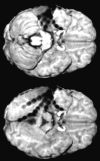

Fig 4.

Lesions beneath the grid or the brain surface (here polymicrogyria) can be highlighted by loading as color-coded overlays and subsequent semitransparent volume rendering. The individual position of each electrode contact with respect to the presumed epileptogenic lesion can be exactly depicted by using yoked coregistered planar MR images alongside the 3D MR imaging data.

Fig 5.

To allow for optimal visualization of electrodes on the posterior basal surface of the brain, the brain extraction (see Fig 1, step 3B) is optionally combined with masking the cerebellum in the skull-stripped postimplantation image.